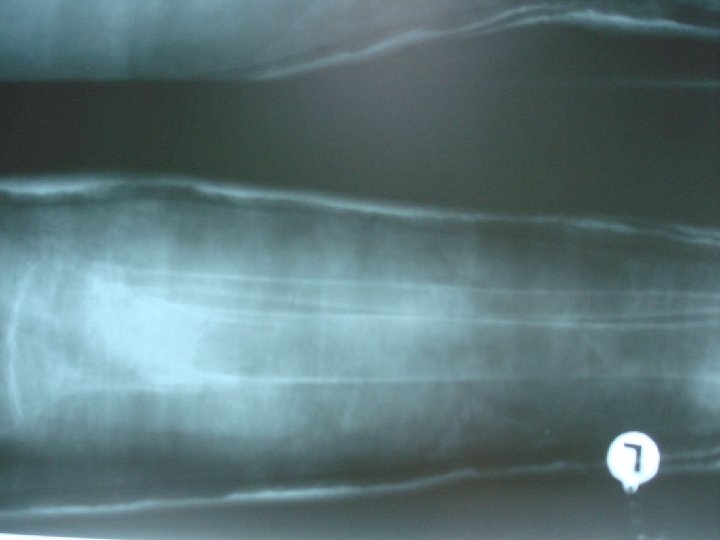

Lytic lesions

Multiple bone cysts and fractures